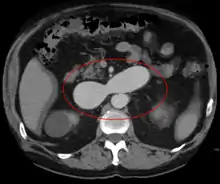

AVMs are diagnosed primarily by the following imaging methods:

- Computerized tomography (CT) scan is a noninvasive X-ray to view the anatomical structures within the brain to detect blood in or around the brain. A newer technology called CT angiography involves the injection of contrast into the blood stream to view the arteries of the brain. This type of test provides the best pictures of blood vessels through angiography and soft tissues through CT.

- Magnetic resonance imaging (MRI) scan is a noninvasive test, which uses a magnetic field and radio-frequency waves to give a detailed view of the soft tissues of the brain.

- Magnetic resonance angiography (MRA) – scans created using magnetic resonance imaging to specifically image the blood vessels and structures of the brain. A magnetic resonance angiogram can be an invasive procedure, involving the introduction of contrast dyes (e.g., gadolinium MR contrast agents) into the vasculature of a patient using a catheter inserted into an artery and passed through the blood vessels to the brain. Once the catheter is in place, the contrast dye is injected into the bloodstream and the MR images are taken. Additionally or alternatively, flow-dependent or other contrast-free magnetic resonance imaging techniques can be used to determine the location and other properties of the vasculature.